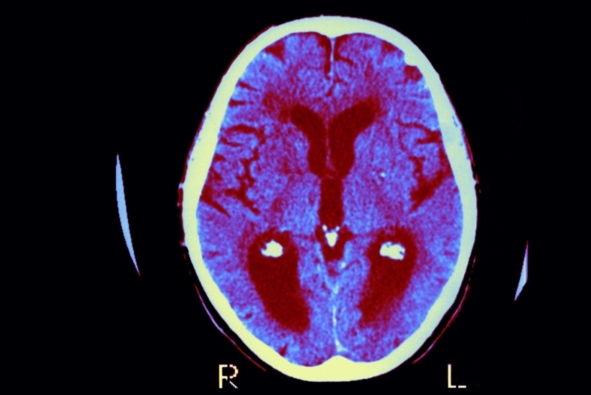

阿尔茨海默病是一种毁灭性的疾病,目前已有超过500万美国人因此丧失了认知能力和记忆功能,而科学家们一直以来都对其发病根源感到困惑不已。但是在一篇即将发表在《阿尔茨海默病杂志》(Journal of Alzheimer's Disease)上且颇引争议的社论中,一批科学家提出导致这一复杂疾病的病因可能很简单:就是一些能引起脑部感染的微生物。这一引人争议的观点并不新奇,长久以来学界都认为它太过荒诞而不予理会,但是越来越多的工作指出这可能是一个值得考虑并深入研究的方向。如果研究人员能证明这一理论,并且能够解释先前引发争议的某些细节(这两项任务都很艰巨,因为有关脑部感染的研究困难重重),那么人们便能从根本上阻止这一疾病的发生。